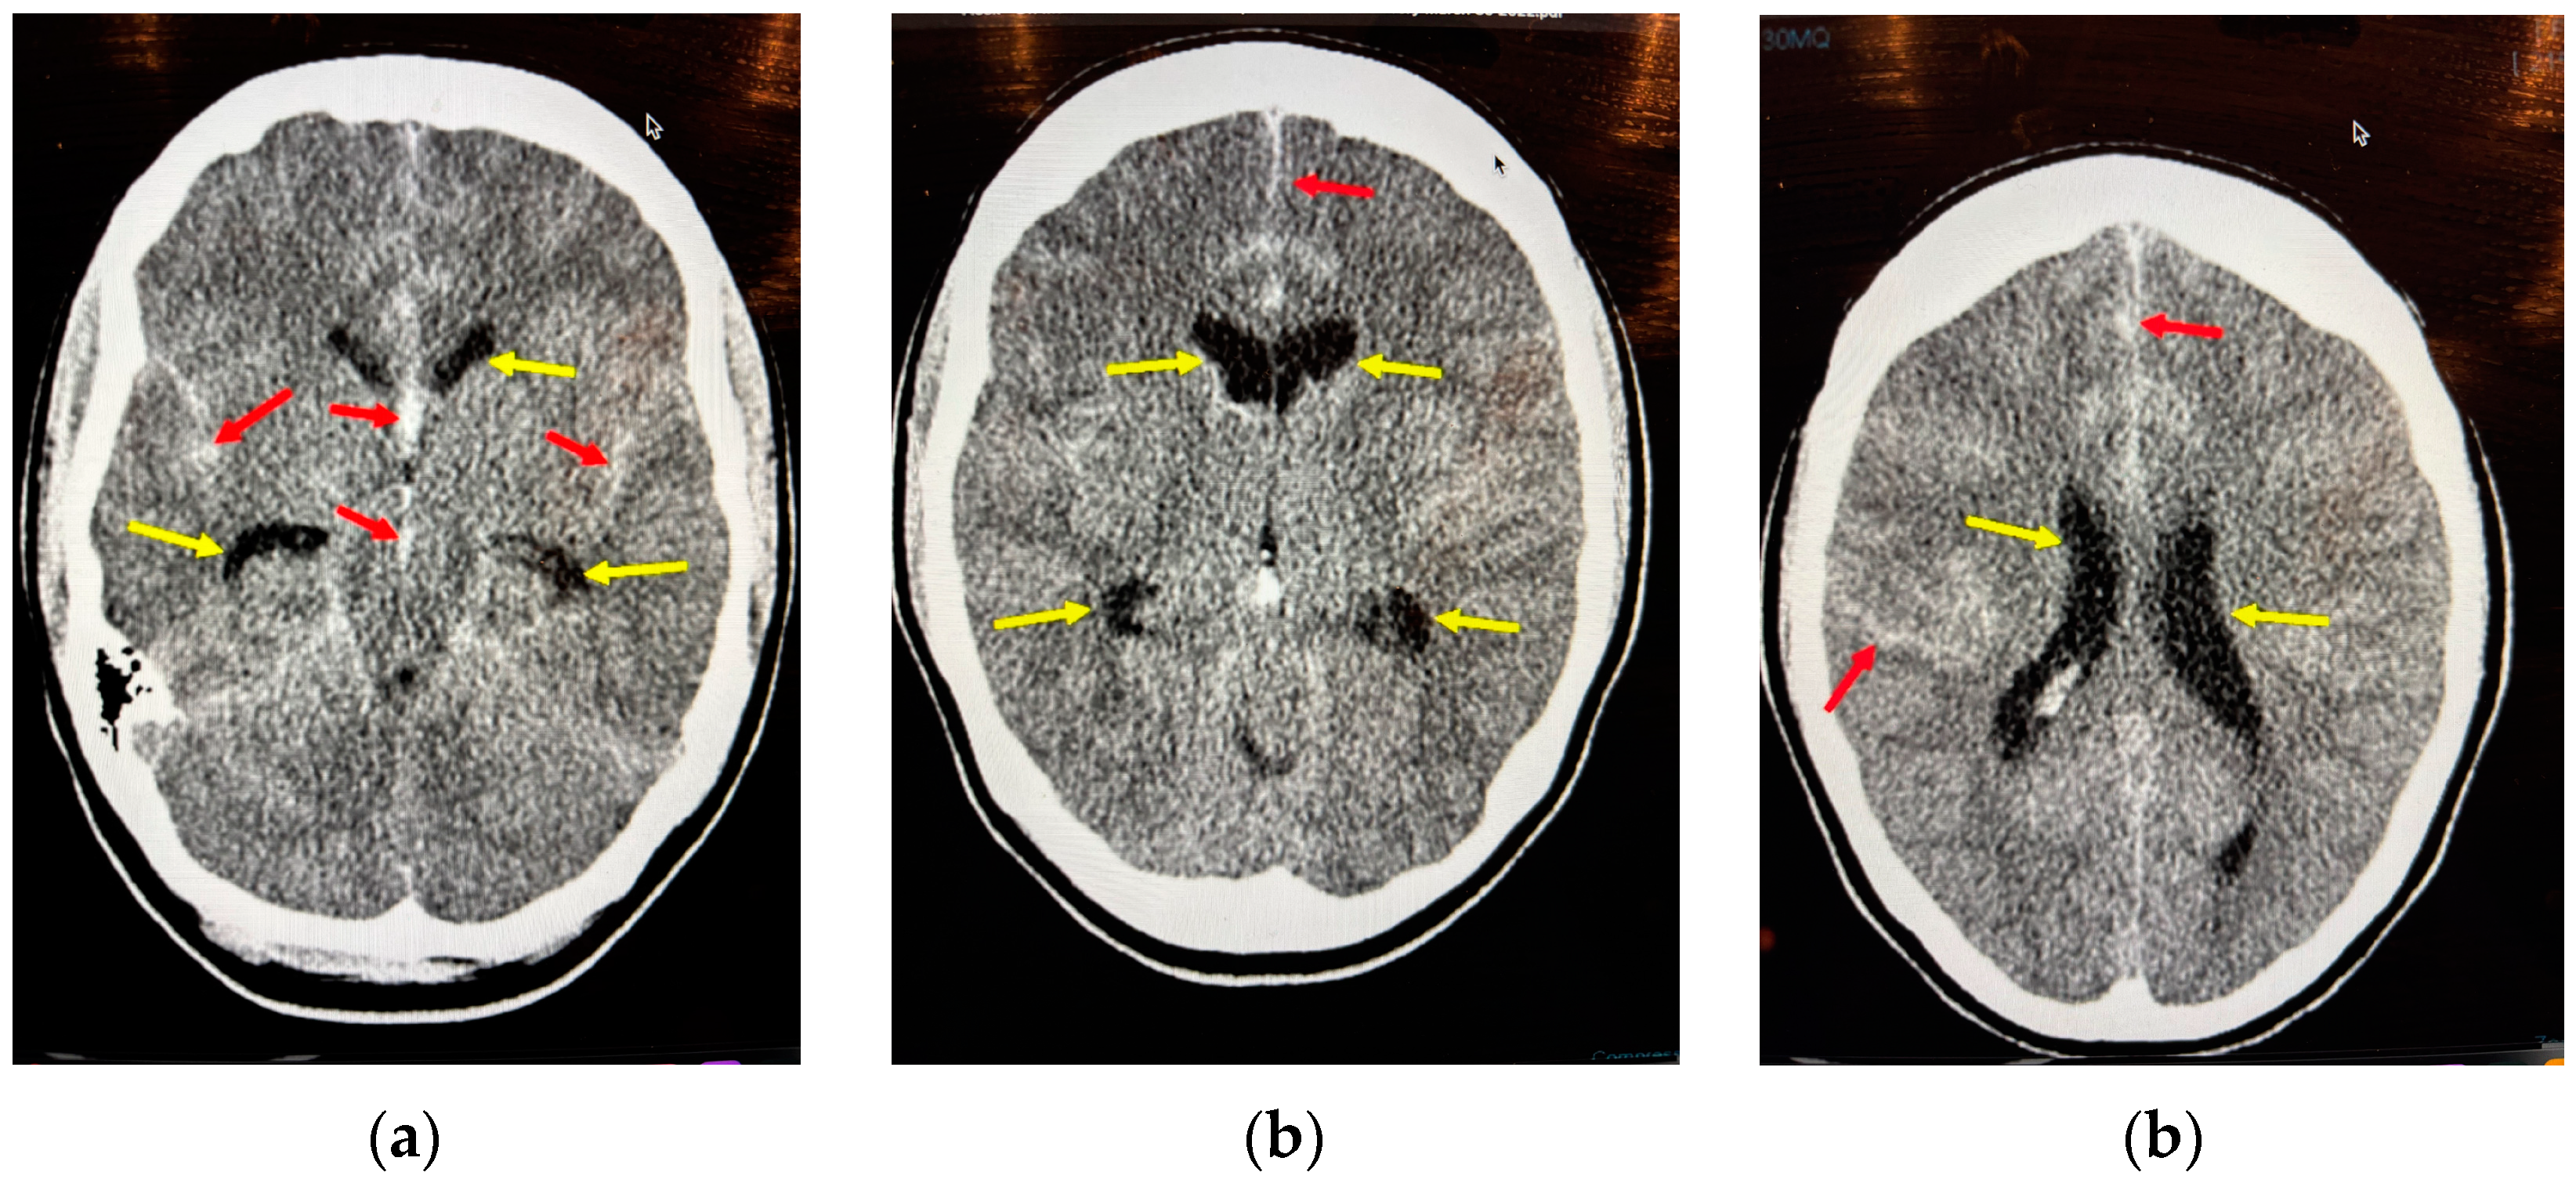

8.2. Acute Hydrocephalus